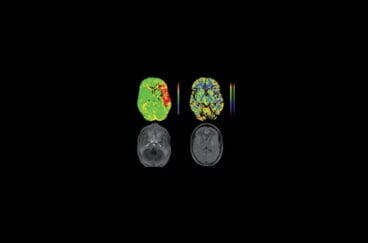

Día mundial del Ictus, una de las enfermedades más limitantes en el mundo occidental29 de octubre de 2015